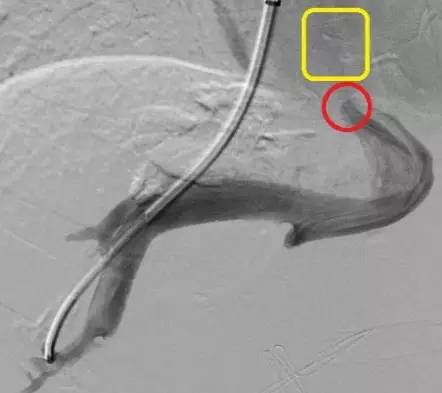

术前

红色圈内为病变的静脉,可见血管极其狭窄,远端黄色方框内未见明显血流通过。